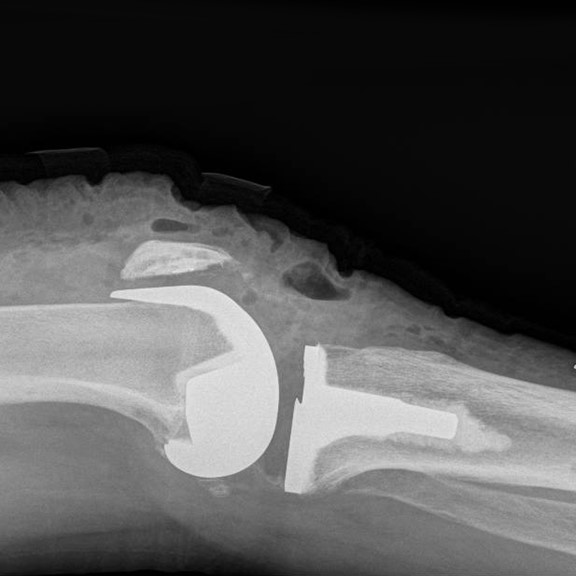

Through a midline incision the surfaces of the bone can be replaced. The femoral component is a smooth metal component of varying sizes, which fits over the end of the femur. The tibial component consists of a metal base plate that sits on top of the tibia and a polyethelene (plastic) insert that fixes onto the tibial component. The patella surface may be replaced if it is worn. The implants are positioned and fixed to the bone using bone cement.